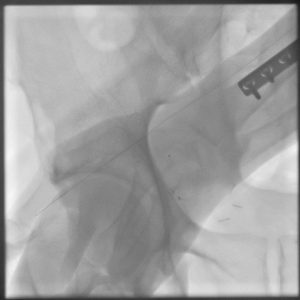

• Fluoroscopy can be used to confirm wire placement within the radial artery prior to placing the sheath if necessary.